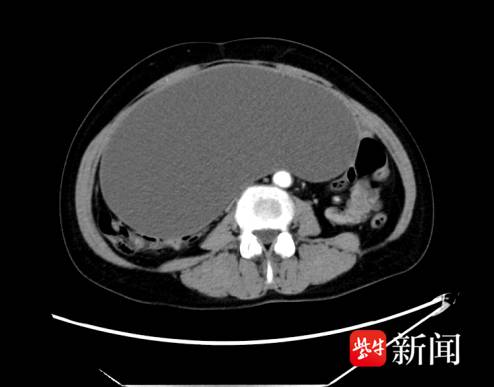

令人震惊的是:通过超声等系列检查,郑女士盆腔内藏着一枚直径约50厘米的巨大多房囊性占位,临床考虑卵巢肿瘤可能性大,随即收治入院。更棘手的是,进一步检查发现其还合并下肢静脉血栓,且包块在短期内迅速增大,手术难度及风险极高。

“这么大的卵巢囊肿非常罕见,包块上缘快贴近肝脏,不仅会压迫周围脏器,术中还可能出现大出血、血栓脱落、脏器损伤等意外。”谭青青介绍,为确保手术安全,医院第一时间启动多学科协作(MDT)机制,召集妇科、麻醉科、ICU、心内科等科室专家紧急会诊。经过反复研讨,团队最终制定了“先吸囊液缩小体积,再完整剥离”的周密方案,决定实施开腹探查术。